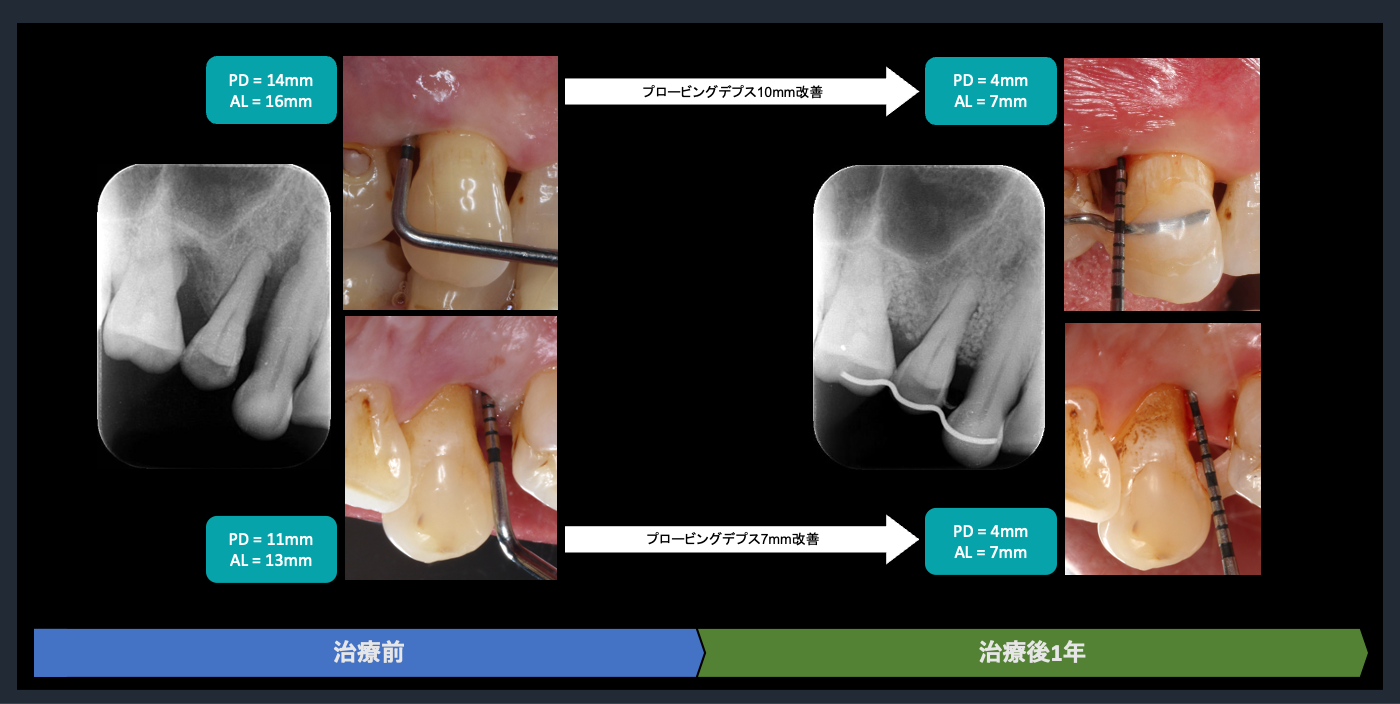

| 概要 | 歯周病が進行しており、右上臼歯部に重度の骨吸収像が認められます。失われた骨を再生し、歯の生存率を高めることを目的に、再生療法を試みました。良好な結果を得ることができました。問題なく使っていただいております。 再生療法を行う利点としては、ポケットが浅くなるので、患者様ご自身でのブラッシングで管理し、コントロールすることが可能になります。もちろん定期的なメインテナンスは必要不可欠です。 |

歯周組織再生療法の評価

Post-treatment evaluation

Post-treatment evaluation

歯周組織再生療法の評価

Post-treatment evaluation

Post-treatment evaluation

歯周組織再生療法の評価

Post-treatment evaluation

Post-treatment evaluation

歯周組織再生療法の評価

Post-treatment evaluation

Post-treatment evaluation

歯周組織再生療法の評価

Post-treatment evaluation

Post-treatment evaluation

歯周組織再生療法の評価

Post-treatment evaluation

Post-treatment evaluation

歯周組織再生療法の評価

Post-treatment evaluation

Post-treatment evaluation